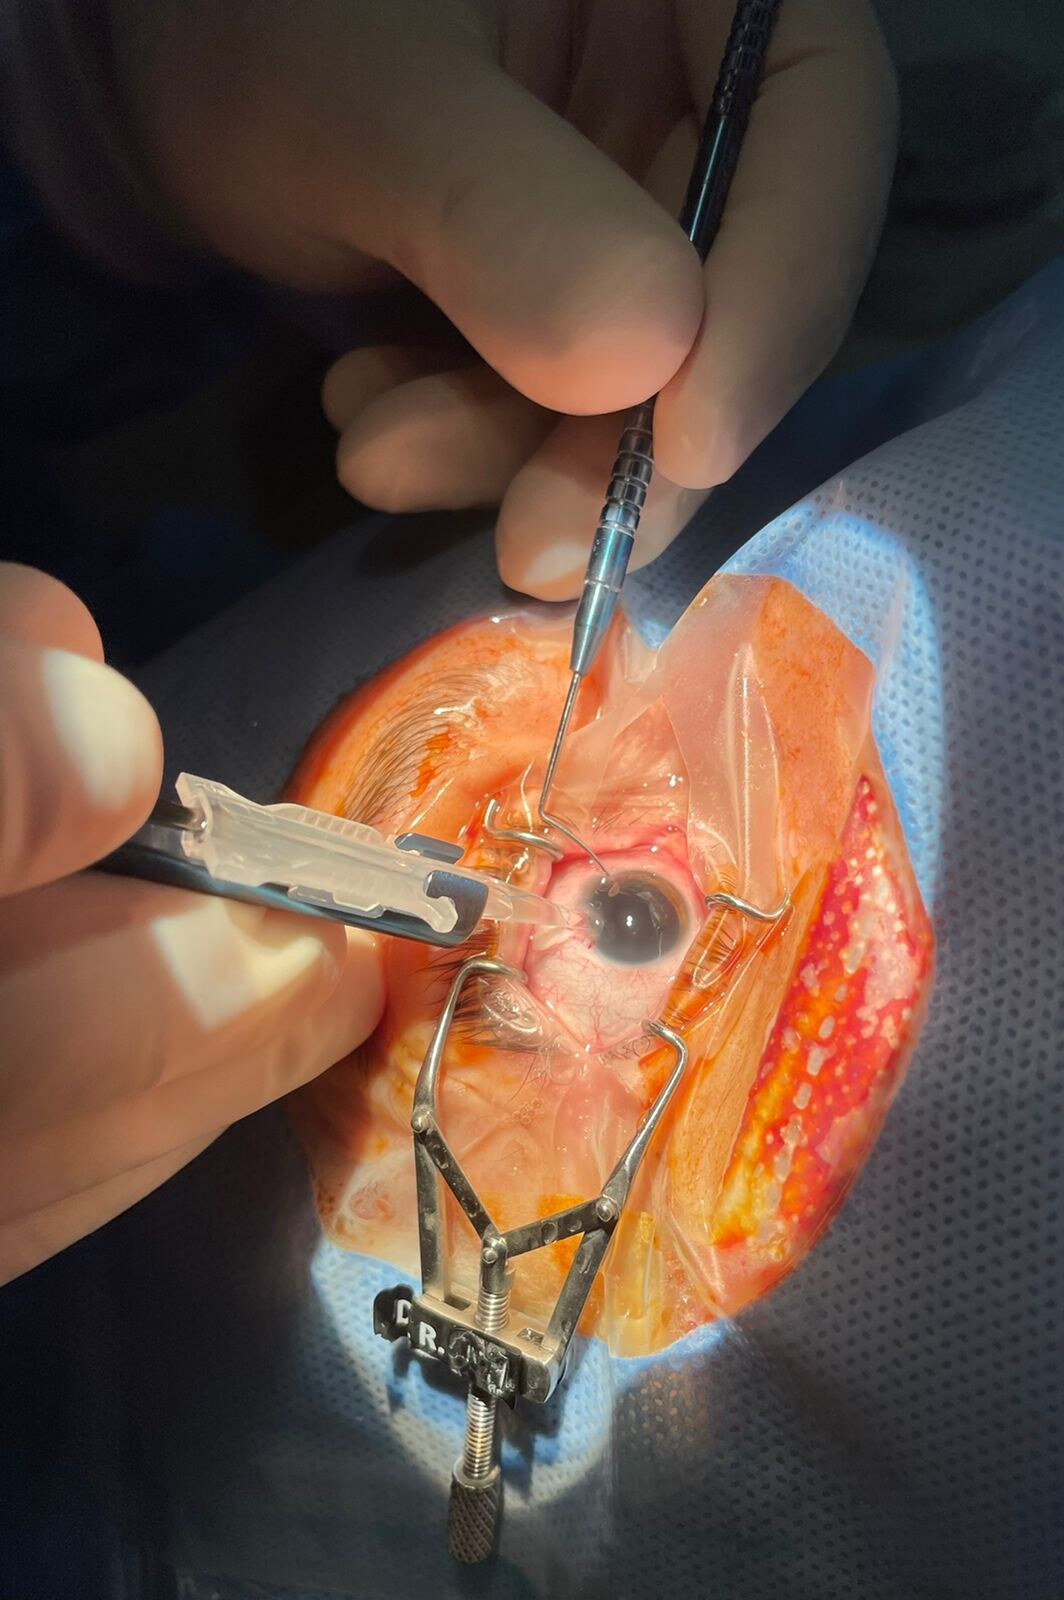

Cirurgia de Catarata Implante de Lente Intraocular

Consiste na retirada do cristalino (lente natural do olho),para implante de uma lente intraocular avaliada, caso a caso, para obter o melhor resultado visual.

A catarata é removida por por facoemulsificacão ou por femtosegundo (cirurgia à laser). A escolha da técnica a ser empregada depende de vários fatores que são orientados pelo cirurgião ao paciente que será operado.